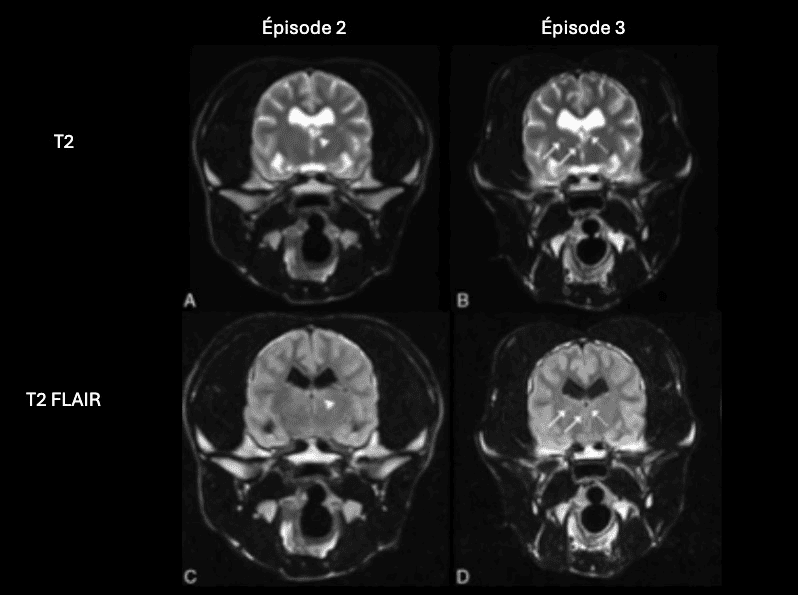

L’IRM est l’imagerie de choix pour ces lésions ischémiques. Les lésions aigues apparaissent hyperintenses sur les séquences T2 et T2 FLAIR, hypointense en pondération T1, et ne montrent pas de rehaussement. L’imagerie en diffusion permet une détection plus précoce de ces lésions. Elle permet également une estimation de l’âge de la lésion et de la taille du noyau infarcié. Les lésions aigues présentent une restriction du signal de diffusion, et apparaissent hyperintense sur la séquence DWI, et hypointenses sur la carte ADC. Les valeurs sur la séquence ADC sont diminuées pendant 4-5 jours, se normalisent entre 4 et 10 jours, et réaugmentent après 10 jours. Ces lésions ne créent pas d’effet de masse, sauf en cas d’œdème vasogénique associé, à son maximum 3-4 jours après l’apparition de la lésion. On peut parfois observer un rehaussement périphérique de la lésion pendant la phase de rupture de la barrière hématoméningée.

En phase chronique, le signal T2 reste stable, mais on observe une réduction progressive du signal en T2 FLAIR. Le signal est parfois mixte sur la séquence T2 FLAIR, en raison de la présence de zones hypointenses d’encéphalomalacie, et de zones hyperintenses de gliose. La taille des lésions diminue en phase chronique, avec atrophie du parenchyme cérébral. Le rehaussement éventuellement présent disparait lors de la restauration de la barrière hématoméningée.